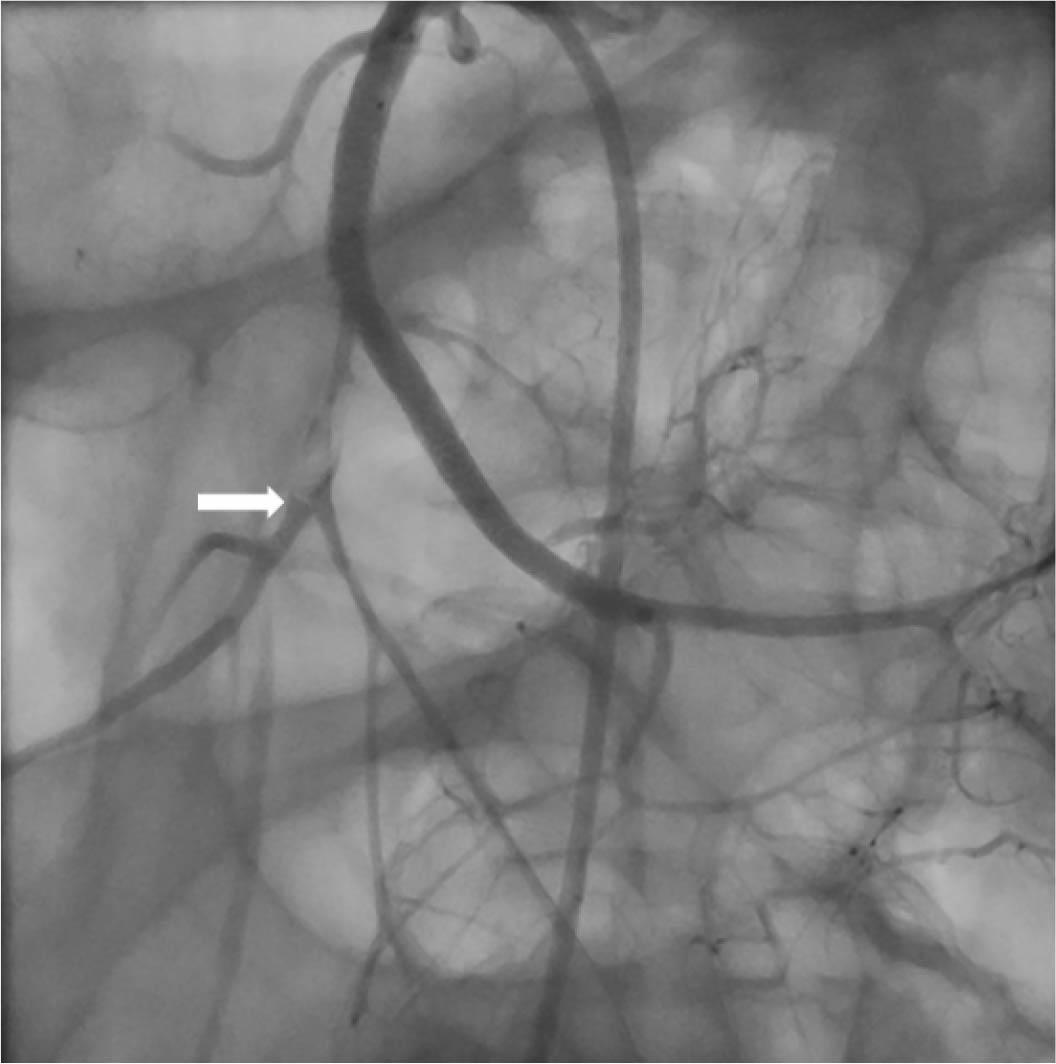

Figure 1